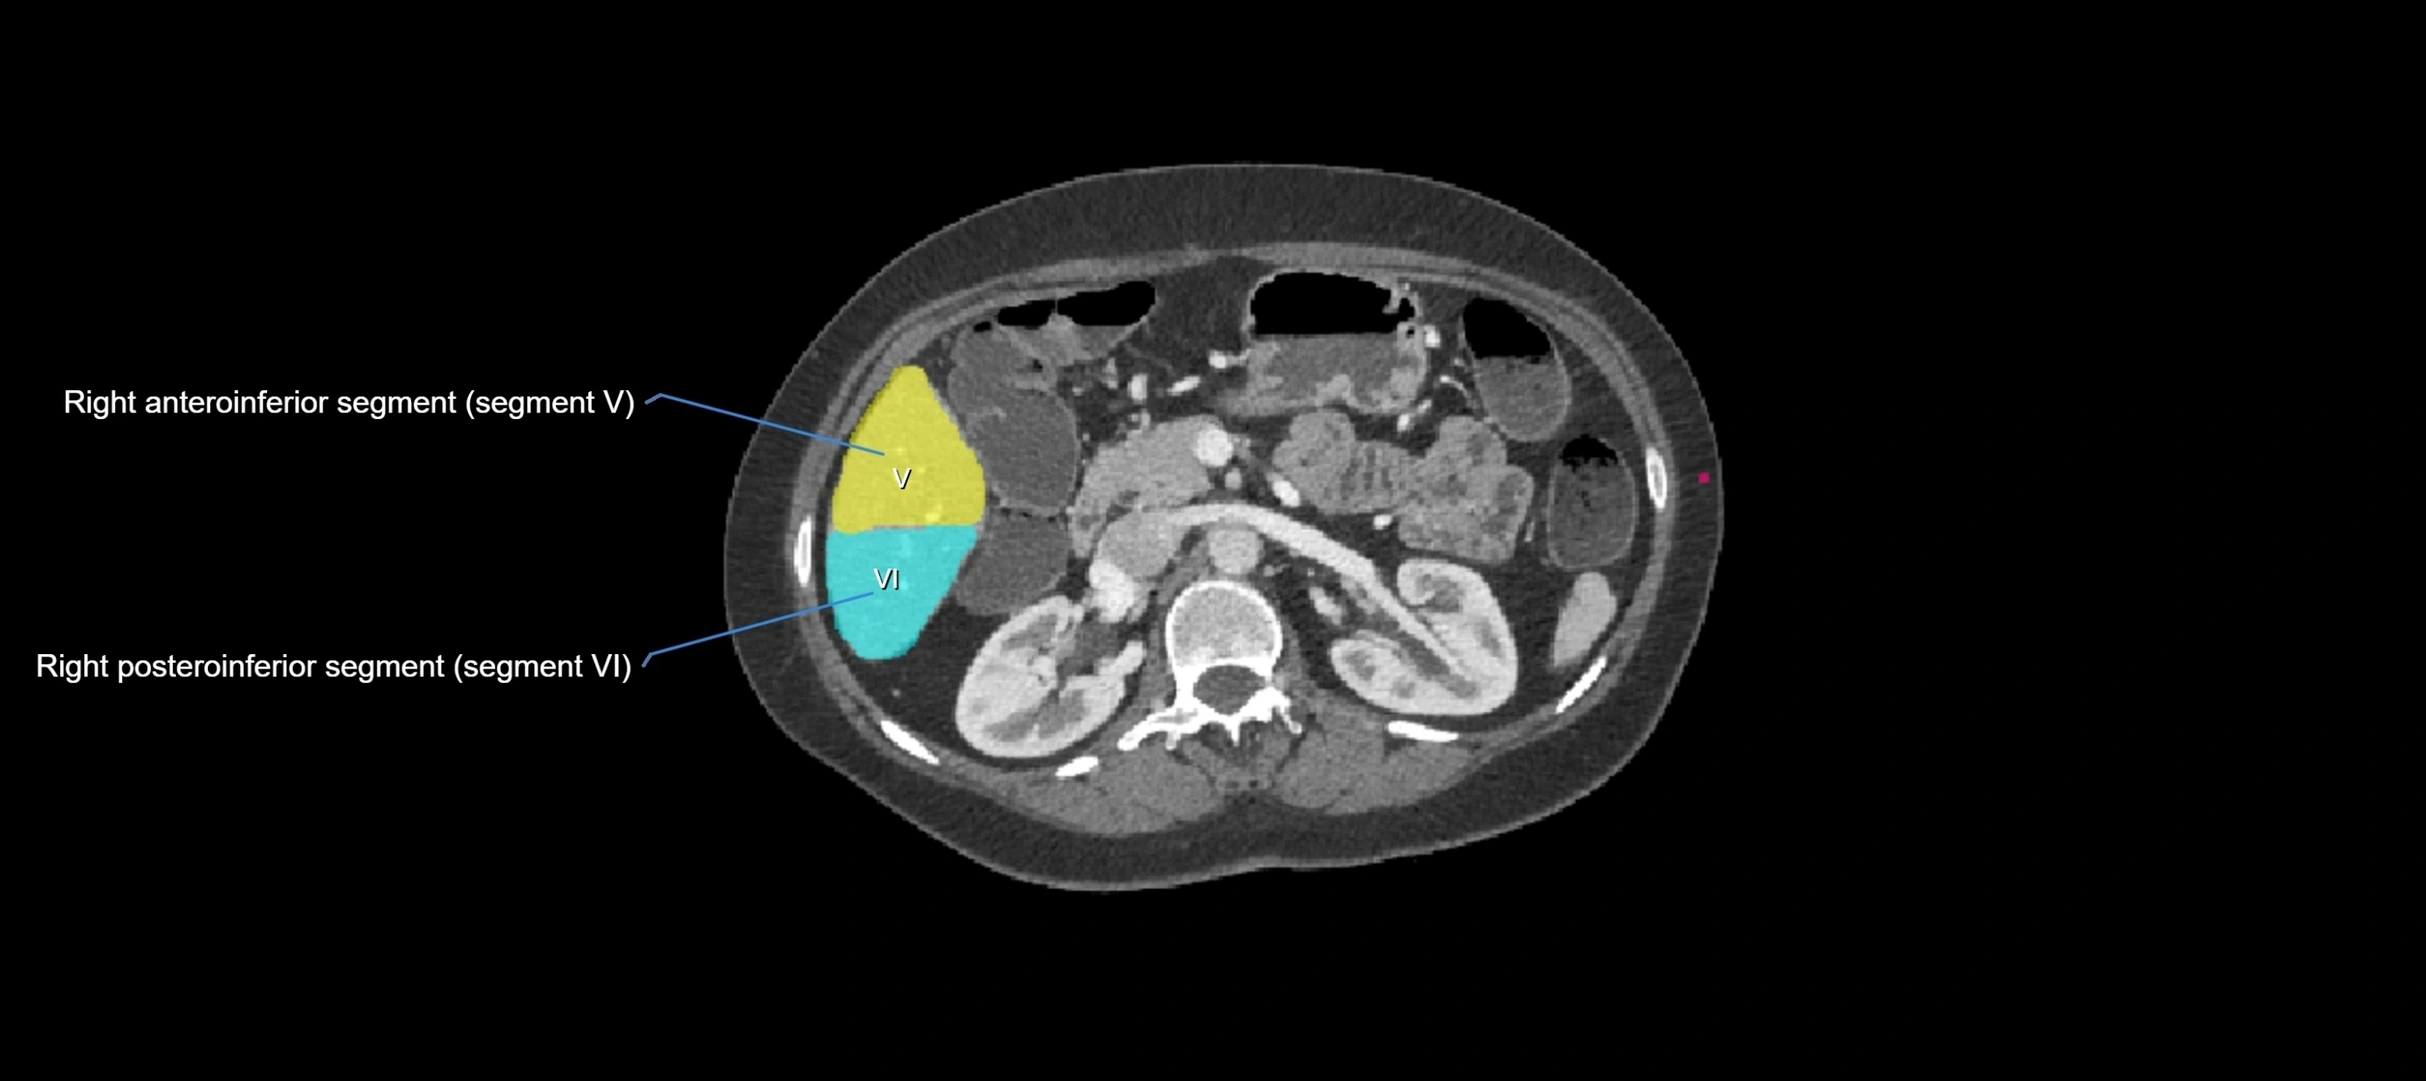

CT Image

image